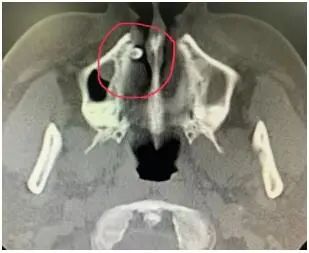

现年三十多的市民庄先生,近段时间以来鼻子一直疼痛不适,前两天来到温州市人民医院耳鼻咽喉科就诊。医生为庄先生安排了鼻内镜及颌面部CT检查。不查不知道,一查吓一跳,庄先生的鼻腔竟然长了一颗类似牙齿的物质。

该院耳鼻咽喉科医生立即联系口腔科医师会诊,最终确定这是一颗长在鼻腔的多生牙。据该院口腔科主任林坚介绍,多生牙病因目前尚不明确,可能是牙齿的牙胚在发育期间受到了刺激,或者是一些遗传因素等多种原因造成多发生了一个牙胚,形成多生牙。

多生牙常见发生于上颌正中,称为正中牙,还有双尖牙区,还能在智齿远中形成,称为第四磨牙。不过,像庄先生一样长在鼻腔的多生牙倒是十分罕见,不仔细检查很有可能造成漏诊和误诊。